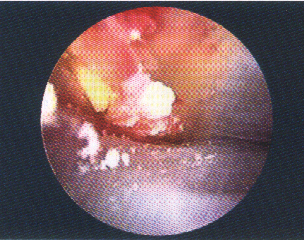

钙化性冈上肌腱炎伴反应性滑膜炎(图1)